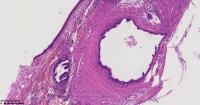

炎性息肉?潴留囊肿?腺体是否有问题?

性别

女

年龄

51岁

临床诊断

一般病史

宫颈赘生物

标本名称

图3

息肉。

稳妥起见最好做一做免疫组化。